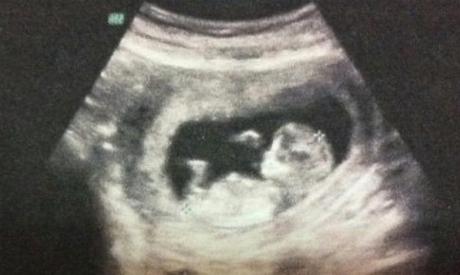

当孕妇怀孕时间超过一定时间后,胎儿已经成型,这个时候药物流产的方式风险会提升,大多数情况下需要进行人工流产。

人工流产的过程其实是很残忍的,这个时候胎儿已经成型,有了心跳。虽然孩子没有任何意识,但已经具备了生命特征。流产的过程也显得十分残酷,首先通过药物让胎儿失去生命,然后采取措施让胎儿顺利排出体外。